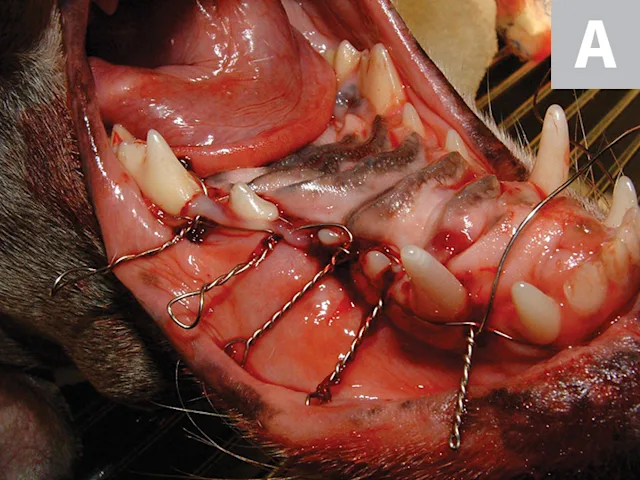

When fracture lines between intact teeth are observed, interdental wiring with 26- to 20-gauge wire at the gingival line of each tooth can be useful as a supplement to other techniques. Acrylic is commonly added over the teeth–wire construct. The teeth should first be scaled, polished, and acid etched, then acrylic should be applied over the teeth–wire construct while ensuring occlusion (Figure 6).4,5 Bone healing may be prolonged if tooth extraction or root canal is required.4 The acrylic and wires can be removed once bone healing is evident, typically 6 to 8 weeks after injury.